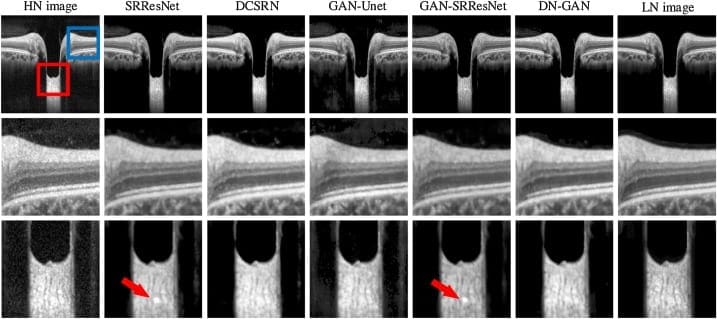

- Denoising — removal of all kinds of noise from the data. For example, removing statistical noise from x-ray images fits medical needs, which will be described in our use cases.

Figure 7. Removing noise from tomography images using GAN (source)

The possibility of image improvement allows us to implement GANs in medicine for Photo-Realistic Single Image Super-Resolution. Why is this significant?

The reason for the high demand for GANs in healthcare is that images should fit particular requirements and be high-quality. High image quality can be difficult to obtain under certain measurement protocols, for example, there is a strong need to decrease the effect of radiation on patients when using low-dose scanning in Computer Tomography (CT, to reduce the harmful effect on people with certain health pre-conditions such as lung cancer) or MRI. It has the effect of complicating efforts to obtain good quality pictures because of the poor quality scans.

Super-resolution improves the captured images and can remove the noise quite well, however adoption of GANs in the medical area is quite slow as many experiments and trials have to be made due to safety concerns. When dealing with healthcare, it is mandatory to involve a number of domain experts to evaluate the models and ensure the denoising does not distort the actual content of the image in some way that could lead to an incorrect diagnosis.